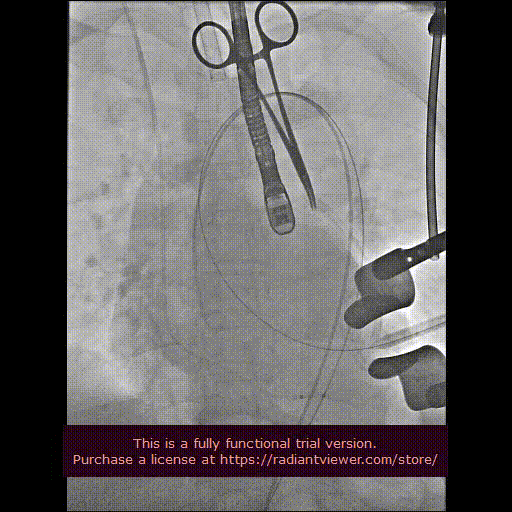

造影显示主动脉窦部

从心尖置入输送系统

定位件入窦

瓣膜降至瓣环平面

释放瓣膜

造影确认瓣膜位置

撤出输送系统

造影确认植入效果